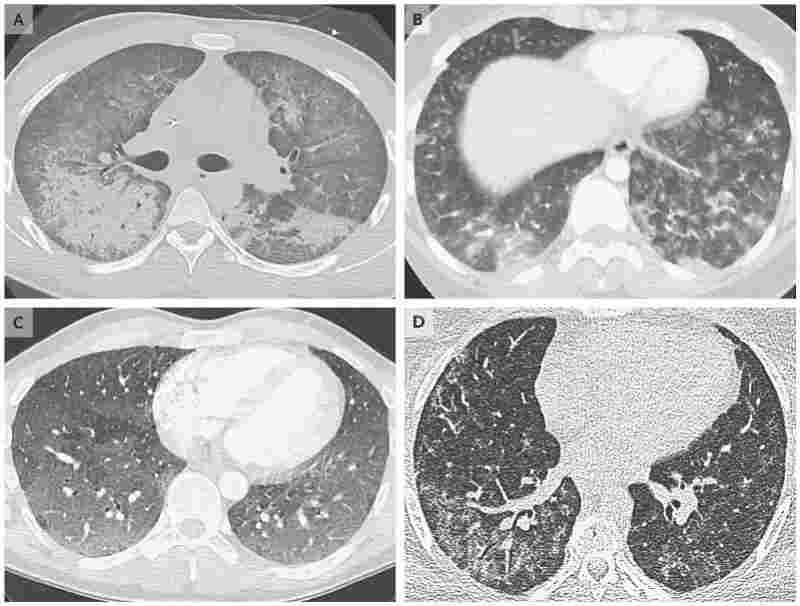

不久后,更多有相似X光照片的患者接連出現,損傷類型高度相似,都十分嚴重,呈現“大白肺”的狀態。

通常,病例在經歷幾天類似流感或肺炎的癥狀之后來到急診室,患者的肺部CT部分區域呈現團狀模糊的白色。七成病例是男性,三分之二的患者在18歲到24歲之間。